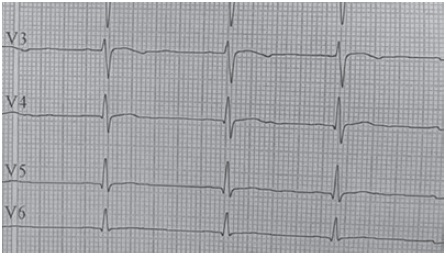

Los laboratorios iniciales muestran un hemograma (Hemoglobina 14,5 g/dL y hematocrito 39,8 %), creatinina (0,65 mg/dL), BUN (17,48 mg/dL), glicemia (72 mg/dL), sodio (137 mmol/L) y uroanálisis normales. Evidencia hipopotasemia (2,6 mmol/L) e hipocloremia (95 mmol/L), cortisol bajo (32 ng/mL con valores de referencia 50-250 ng/mL), renina plasmática baja (4,38 con valores de referencia 20-55 μUI/mL) y un electrocardiograma con hallazgos compatibles con la hipopotasemia (Figura 3). La edad ósea revisada por el método de Greulich y Pyle es de 17 años (Figura 4). En la ecografía renal y de vías urinarias se observa un aumento del tamaño de las glándulas adrenales con diferenciación corticomedular, aspecto más ensanchado de la izquierda, sin evidencia de lesiones focales. El ecocardiograma demostró una cardiomiopatía hipertrófica concéntrica ventricular izquierda no obstructiva, con un aumento de la raíz aórtica e insuficiencia valvular pulmonar leve, sin signos de hipertensión pulmonar. La biomicroscopía del fondo de ojo y agudeza visual se encuentran normales.

La hipopotasemia usualmente tiene manifestaciones clínicas como fatiga, debilidad muscular, parálisis y alteraciones electrocardiográficas15. Se evidenció en el caso presentado una hipopotasemia moderada sin los síntomas anteriormente mencionados, pero sí se observaron los cambios electrocardiográficos, similares a los reportados por Rustagi et al.16. La hipopotasemia se relaciona con la sobre estimulación del receptor de mineralocorticoide, lo cual produce eliminación de potasio en el túbulo contorneado distal y reabsorción de sodio. Cifras tensionales altas y valores bajos de potasio, son individualmente inhibidores de la síntesis de la renina a nivel yuxtaglomerular6, lo que explica la HTA con la actividad de la renina plasmática baja presente en nuestro caso. Por ello se recomienda incluir antihipertensivos ahorradores de potasio como la espirinolactona.